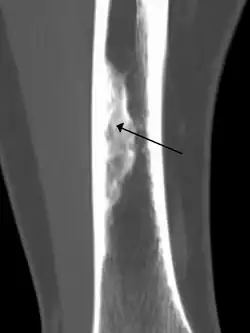

Diagnosis is by X-ray or MRI, usually when investigating a person for something else.[2] Medical imaging typically shows a well defined radiolucent lesion, with a distinct multilocular appearance, sometimes looking like bubbles.[2] It is usually around 1–2 cm in size, but be as large as 7 cm.[3] They consist of foci consist of collagen rich connective tissue, fibroblasts, histiocytes and osteoclasts.[2] Usually no treatment is required.[1] Surgical curettage and bone grafting may be required if it is large.[3]

It is usually diagnosed by x-ray or MRI, when investigating another problem.[1] The tumor presents as a well defined radiolucent lesion, with a distinct multilocular appearance, sometimes looking like a "soap bubble".[5] If small and no symptoms, then biopsy is not needed.[1]